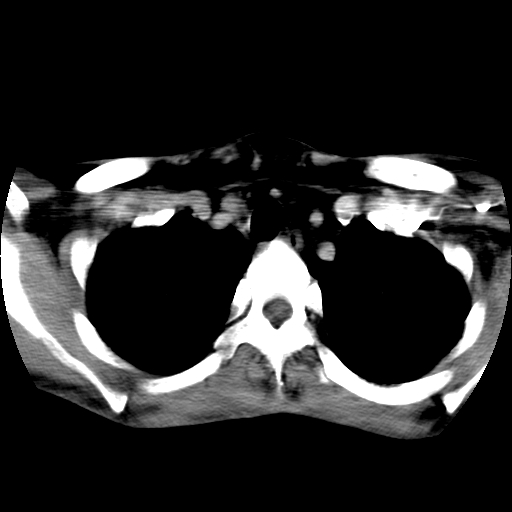

标题: CT24019:男,45岁,发现颈部肿物5个月。 [打印本页]

男,45岁,发现颈部肿物5个月,彩超示:双侧颈部及下颌部软组织增厚。

考虑双侧颈项部良性对称性脂肪增多症。

双侧颈项部脂肪沉积